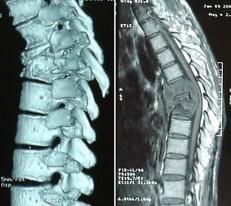

2.CT

CT檢查可以清晰地顯示病灶部位,有無空洞和死骨形成。即使是小型的椎旁膿腫,在CT上檢查時也可發現。CT檢查對腰大肌膿腫有獨特的價值。

3.MRI

MRI具有早期診斷的價值,在炎性浸潤階段即可顯示異常信號,但主要用於觀察脊髓有無受壓和變性。